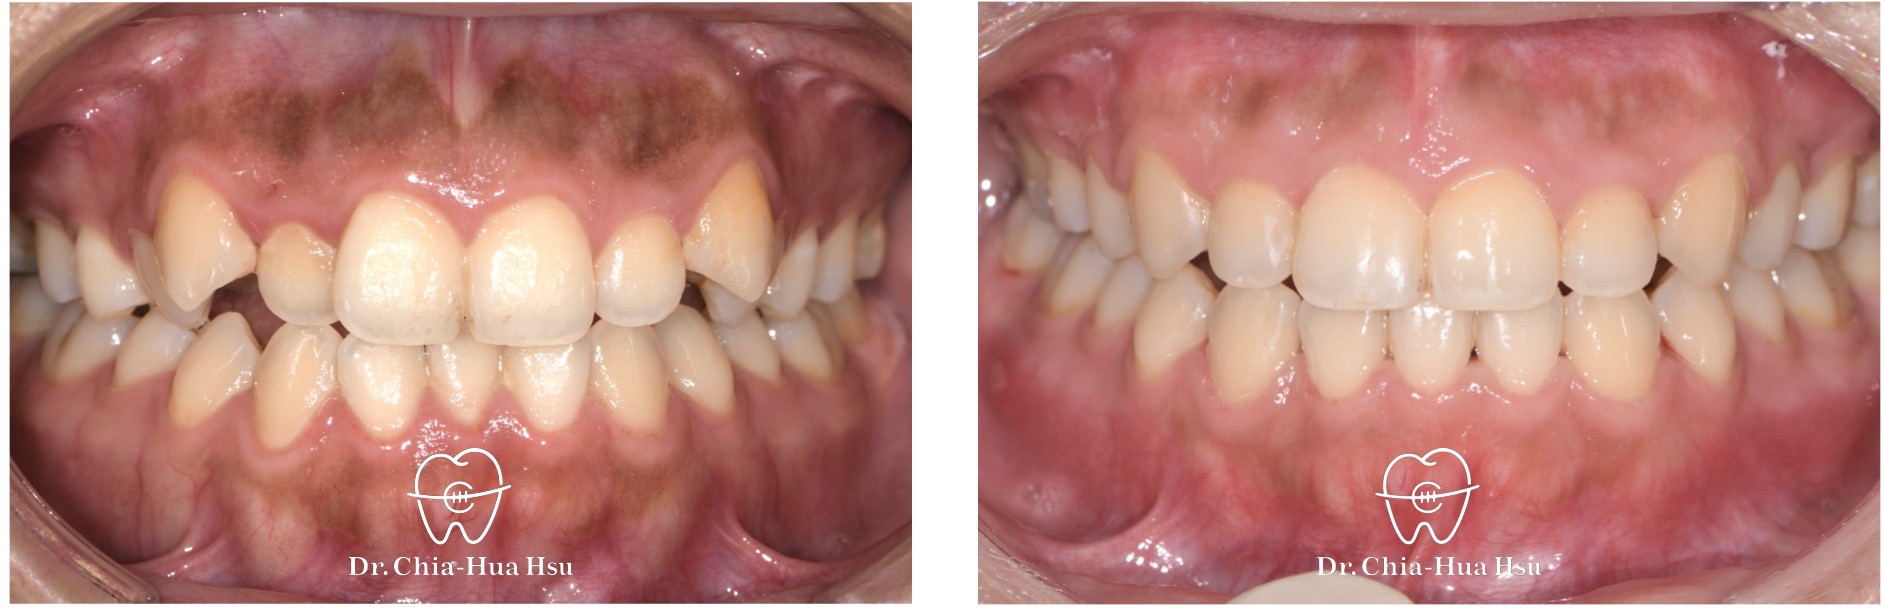

治療前

治療後

- 「笑齦」(Gummy Smile)是指微笑時露出牙齦的比例過多,通常定義為微笑時牙齦露出超過 3 毫米。有些人覺得這樣的笑容可愛自然,但也有人會覺得笑齦讓牙齒看起來短,或影響整體美觀。

- 「笑齦」原因可能有:上唇活動度較大 → 微笑時上唇抬得很高,牙齦容易外露。牙齒萌出位置較低或牙冠偏短 → 牙齒比例看起來小,牙齦顯得多。牙齦增生 → 牙齦組織因發炎、藥物或其他因素變多。上顎骨垂直過度生長 → 骨性問題導致牙齦露出比例增加。